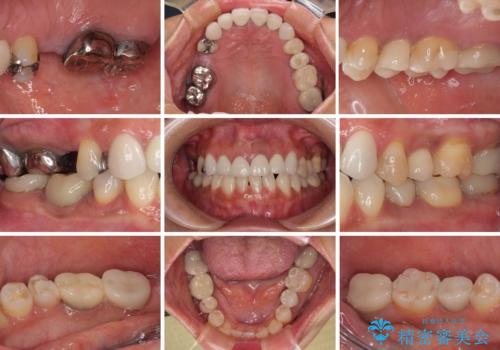

新幹線通院 地元で断られた奥歯のむし歯治療

- 地元の歯科医院で治療を行っていたものの、難しいので都会に行くように指示をされたとのことで来院された患者様です。

右下のむし歯が歯肉縁下に及んでおり、歯周外科処置(歯冠長延長術)を行った上で、根管治療を行い、状態を整えて補綴治療を行うこととしました。

上顎前歯の根尖病変に痛みがありましたが、既に前歯が補綴治療済みであっため、外科的歯内療法(歯根端切除術)を行うことで解決することとしました。

新幹線で通院をされていたため、極力診療回数を減らして、一度にまとめて多くの処置を行うことで負担を軽減しました。